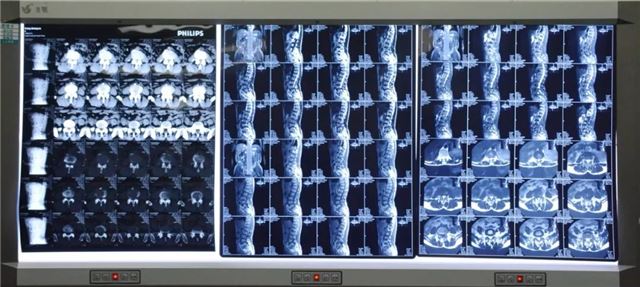

辅助检查

入院后腰椎间盘CT显示:L3/4、L4/5椎间盘膨出、L4/5椎间盘突出,L退行性改变、L4椎体向前滑脱移位。诊断为:“腰椎管狭窄综合征”及“L4椎体1°滑脱”。